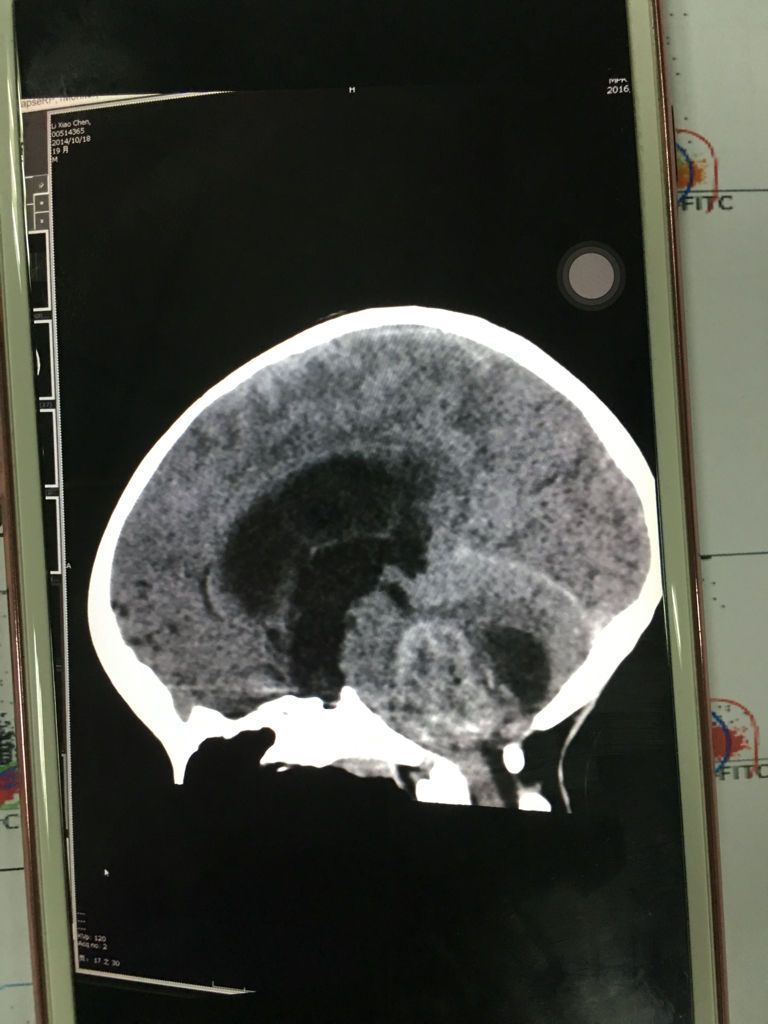

你所说的水母细胞瘤应该是:髓母细胞瘤,它是一种好发于儿童的颅内恶性肿瘤,是中枢神经系统恶性程度最高的神经上皮性肿瘤之一,主要表怪细现为颅内压增高和共济失调等小脑症状常有点堡复视及多种脑神经障碍。医生的孟毯玻意见主要是手术切除与术后放射治疗,部分病例可辅以化疗。